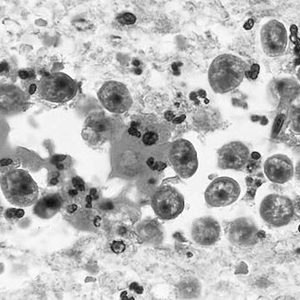

食脑虫感染者脑组织照片。